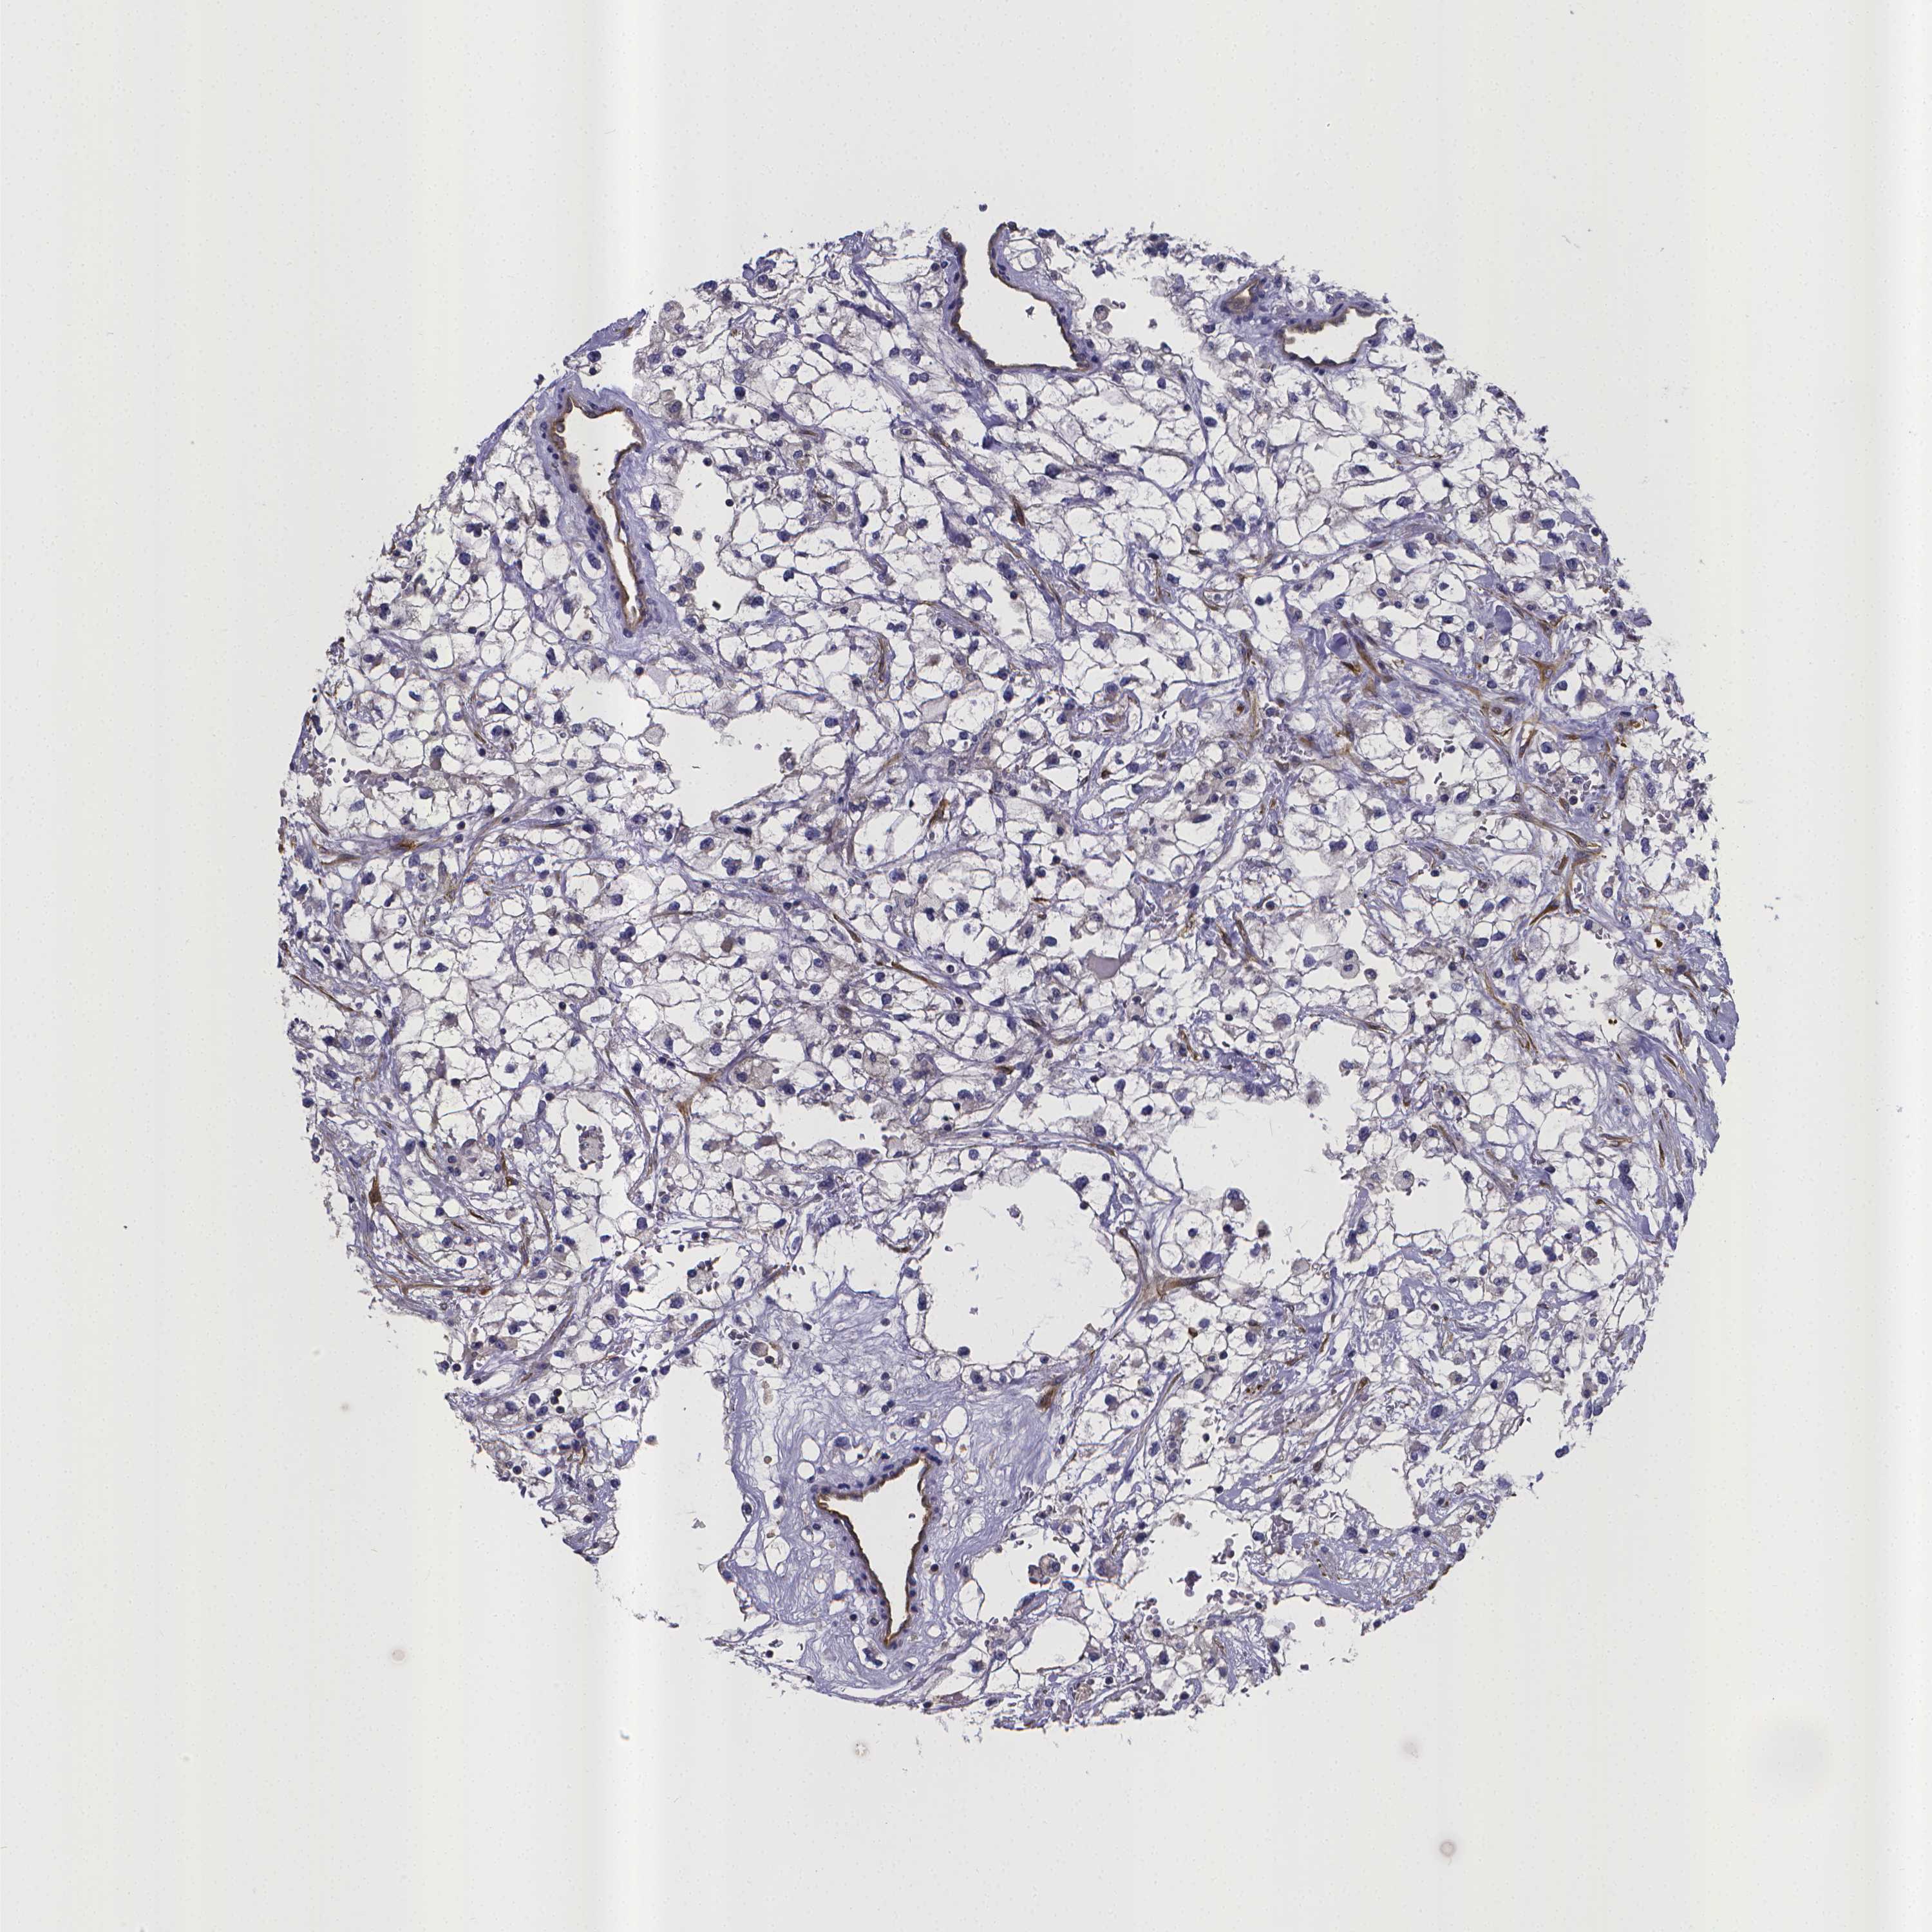

CANCER RENAL CANCER Show tissue menu

KICH TCGA KIRC TCGA KIRC VALIDATION KIRP TCGA PROTEIN RCC CPTAC PROTEIN EXPRESSION

Kidney renal clear cell carcinoma